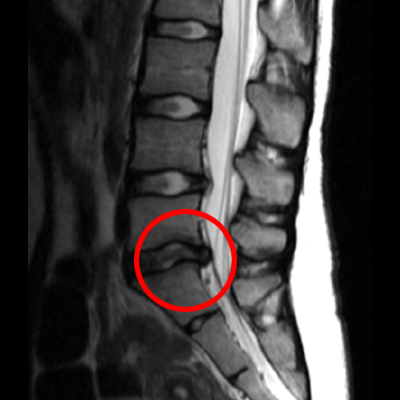

교통사고 후 mri 촬영내용에서

요추5번 및 천추 사이 디스크가

심각하게 돌출된 것이 보여집니다.